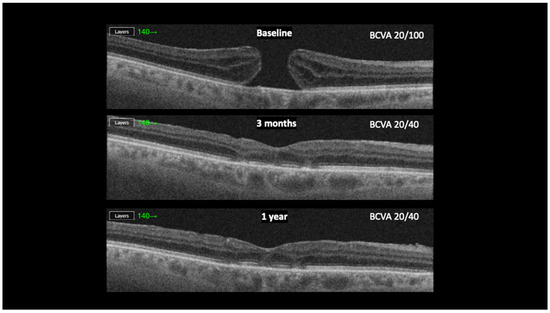

Background: The purpose of this study was to evaluate the anatomical and visual outcomes of patients with stage IV full-thickness macular holes (FTMHs) treated by the cabbage leaf inverted internal limiting membrane (ILM) flap technique. Methods: We conducted a retrospective study, enrolling patients [...] Read more.

Background: The purpose of this study was to evaluate the anatomical and visual outcomes of patients with stage IV full-thickness macular holes (FTMHs) treated by the cabbage leaf inverted internal limiting membrane (ILM) flap technique. Methods: We conducted a retrospective study, enrolling patients with stage IV FTMH operated by a single surgeon. Six patients with FTMH and no other known ocular comorbidities were included in the study. Results: Four patients (66.6%) were female, two were male. The median age was 71. The average duration of symptoms before surgery was 10.5 months (6–24 months). The mean preoperative minimum hole diameter was 480 μm (337–602), and the mean basal hole size was 1208 μm (703–1748). The mean preoperative BCVA was 0.63 LogMAR. Postoperatively, the BCVA improved in 5 (83.3%) patients and remained the same in 1 (16.7%). The mean postoperative BCVA was 0.42 LogMAR (0.0–0.70). The FTMH has closed in all cases (100%). At the follow-up examination three months after the surgery, we observed complete closure of the FTMH with the restoration of retinal layers. Conclusions: This approach resulted in a complete closure of FTMH with significant visual acuity improvement. The technique could represent the surgical procedure of choice in the management of stage IV FTMH. Full article